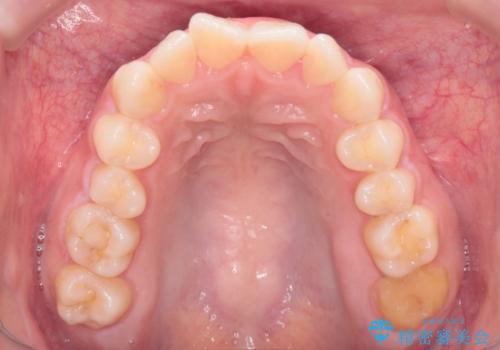

- 患者様は、上下顎の歯列不正と前歯部の突出感を主訴としてご来院されました。診断の結果、上顎左右第一小臼歯を抜歯することでスペースを確保し、歯列全体を整える方針としました。本来はワイヤー矯正が推奨されるケースですが、患者様のご希望により、透明なマウスピース型矯正装置「インビザライン」を使用した治療計画を立案しました。治療期間は約3年で、奥歯の噛み合わせを維持しながら、徐々に前歯の位置を整えました。

インビザラインは見た目の目立ちにくさと取り外しが可能な点がメリットですが、複雑なケースでは治療計画の精密さが求められます。本症例では奥歯の噛み合わせが崩れないよう注意を払いながら、マウスピースの交換タイミングを細かく設定しました。患者様には装着時間を守っていただくことが重要で、1日20時間以上の装着が必須です。また、抜歯部位のスペースを閉じる過程で、歯の動きが停滞しやすい時期もあるため、定期的なチェックを通じて治療が順調に進むよう管理しました。